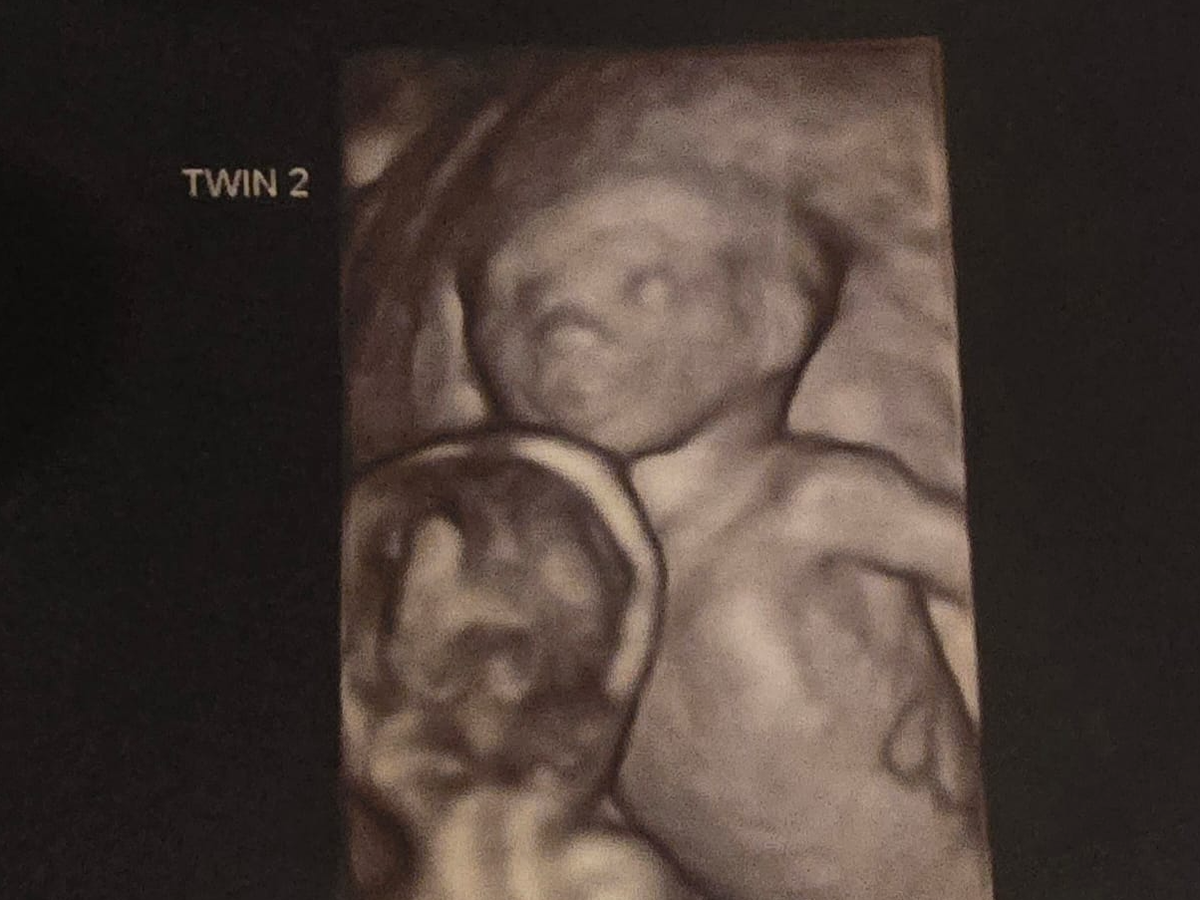

So we went to our 12week scan to surprisingly find out we are having identical twins. This was a big shock! But very happy to find this out. We then went to our 16weeek scan to find out that 1 baby is behind by 1 week compared to the other this is called TTTS with twin 1 being smaller and not getting enough fluid then twin 2 this is called - TWIN TO TWIN TRANSFUSION SYNDROME. We now have been refered to St George's twin specialist hospital in London to monitor and to have laser treatment to make sure they give both twins a good fighting start and to give the other twin that's developing behind more blood flow and nutrients.